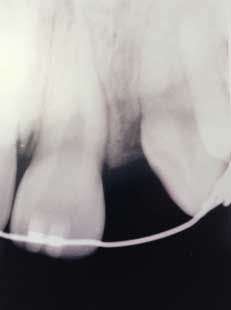

The following case study shows a Caucasian male, age 15 at the beginning of treatment. He had a peg lateral incisor No. 7 and was congenitally missing tooth No. 10. The treatment plan consisted of positioning tooth No. 7 for a veneer and opening space for an implant to replace tooth No. 10. After 30 months of orthodontic treatment had elapsed, there was still insufficient room for implant placement. There was sufficient room for the crown of No. 10, but the roots of teeth Nos. 9 and 11 were still too convergent to allow implant placement. The patient was leaving for college soon and was anxious to have treatment completed. The decision was made to have a periodontist do a corticotomy surgery to accelerate the tooth movement.

Corticotomy surgery was done and distal root movement was initiated on tooth No. 11 using a lever arm and elastic power chain. Root divergence was accomplished in eight weeks, and implant placement was accomplished at that time. The occlusion was detailed and orthodontic appliances were removed a short time later.